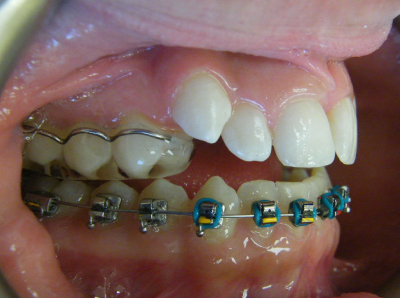

The first two sets of photos below are the before and after photos of a patient who had expansion of the upper jaw followed by upper and lower fixed braces. The third set of photos shows a patient with an expansion plate bonded to the upper teeth and lower fixed braces.